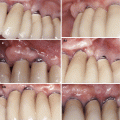

Fig. 3.1

Some potential aetiologic agents associated to the development of gingival recessions. Teeth crowding (a), reduced thickness of the alveolar bone plate (b), muscular inserts close the gingival margin + dental biofilm accumulation (c), periodontitis (d), improper extraction of a supernumerary tooth (e), trauma (oral piercing) (f), ortodontic tooth movement beyond the buccal alveolar bone plate (g), traumatic toothbrushing (h), lack of keratinised gingiva (i)